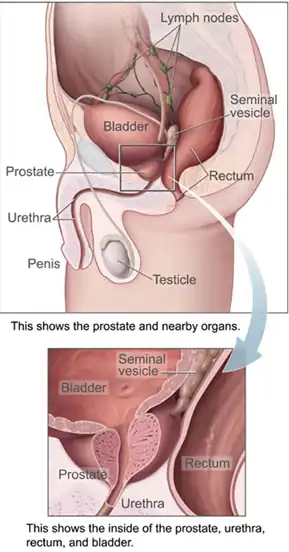

Anatomia masculina

A próstata é uma glândula exócrina do sistema reprodutor masculino encontrada apenas em alguns mamíferos. Ela difere entre as espécies anatomicamente, quimicamente e fisiologicamente. Anatomicamente, a próstata encontra-se abaixo da bexiga, com a uretra passando por ela. É descrito na anatomia geral como consistindo de lóbulos e na microanatomia por zona. É circundado por uma cápsula fibromuscular e contém tecido glandular, bem como tecido conjuntivo.

Estrutura

A próstata é uma glândula exócrina do sistema reprodutor masculino. Em adultos, é do tamanho de uma noz,[1] e tem um peso médio de cerca de 11 gramas, normalmente variando entre 7 e 16 gramas.[2] A próstata está localizada na pelve. Ele fica abaixo da bexiga urinária e envolve a uretra. A parte da uretra que passa por ela é chamada de uretra prostática, que se une aos dois ductos ejaculatórios.[1] A próstata é coberta por uma superfície chamada cápsula prostática ou fáscia prostática.[3]